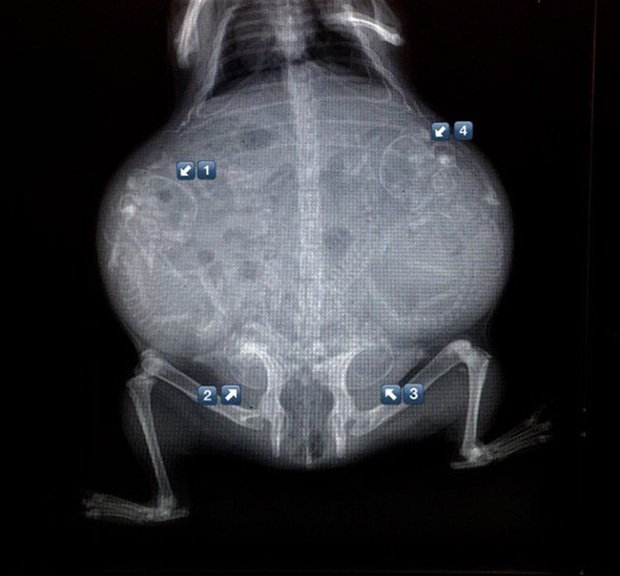

Ảnh chụp X-quang một con chuột lang đang mang thai.

Cận cảnh hình chụp X-quang một cô mèo đang mang thai và loạt ảnh động vật mang bầu khiến người xem rùng mình nhưng rồi thấy đẹp khó tả - Ảnh 8.